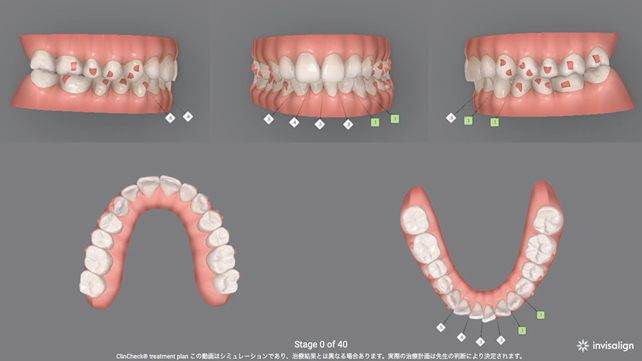

インビザライン®︎と呼ばれる透明なマウスピースを用いて、正常な噛み合わせを作るための設計を行いました。

インビザライン・ジャパン株式会社より(https://www.invisalign.co.jp/)

今回のケースでは、以下のようなシミュレーションを組んで治療しました。

ポイントは先に挙げた3つの問題の解決です。

1.歯全体で噛めず、奥歯だけが強く当たる状態になっていた

2.前歯の凸凹の影響で、歯本来の機能が働かなくなっている

3.上の歯列が右下がりになっている